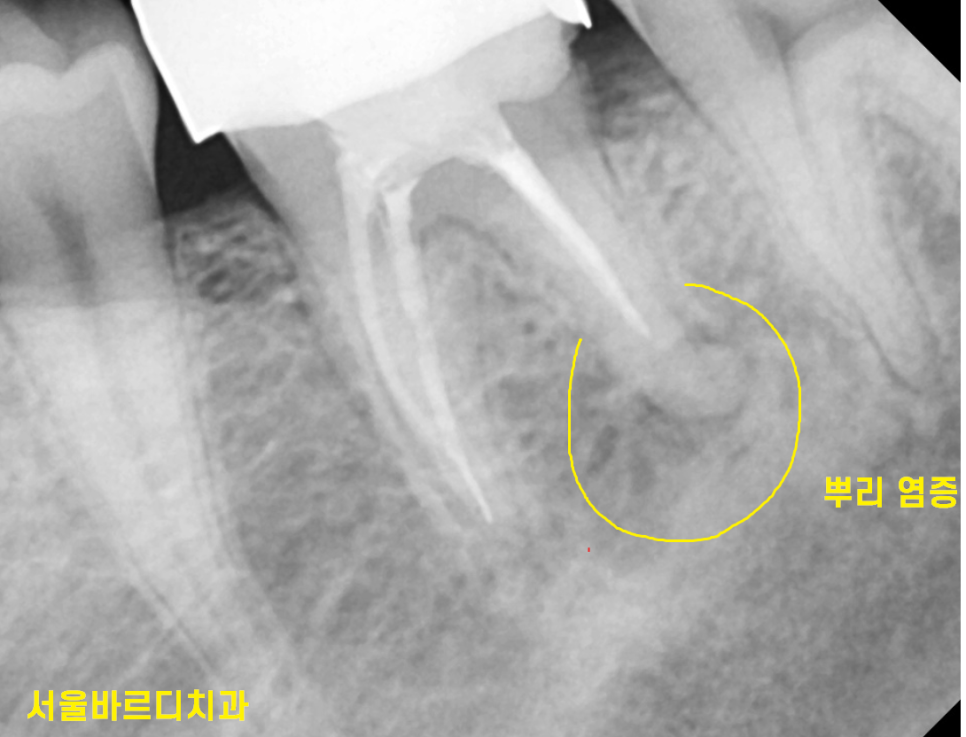

예전에 치료했던 치아가 염증이 자꾸 생겨 서울 바르디치과를 찾아와주셨는데요.

치아의 충치가 심하거나

뿌리에 염증이 있을 때 치료를 하는 것이 신경치료인데요.

신경치료 후에 염증이 발생

환자분이 통증이나 불편함을 호소하는 경우가 있습니다.

220718 신경치료 염증 발생하면 잇몸 뼈가 녹아요!

230727 염증 크기가 어마무시하죠~??